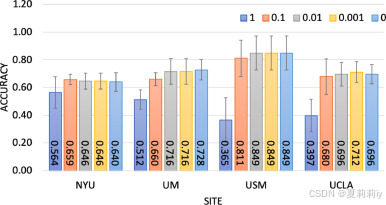

⑪Adding Laplace noise to local weight and varying

: